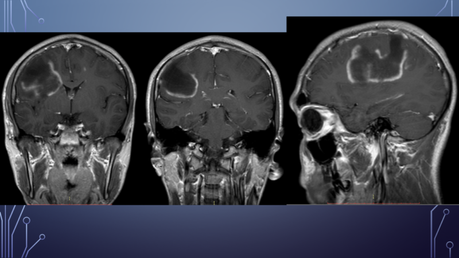

El paciente es diagnosticado con EM.

Deterioro neurológico: parálisis de miembro superior izquierdo y hemiparesia izquierda.

Ingresa al HGZ en Cancún, Q. Roo, con traslado a la UMAE Mérida